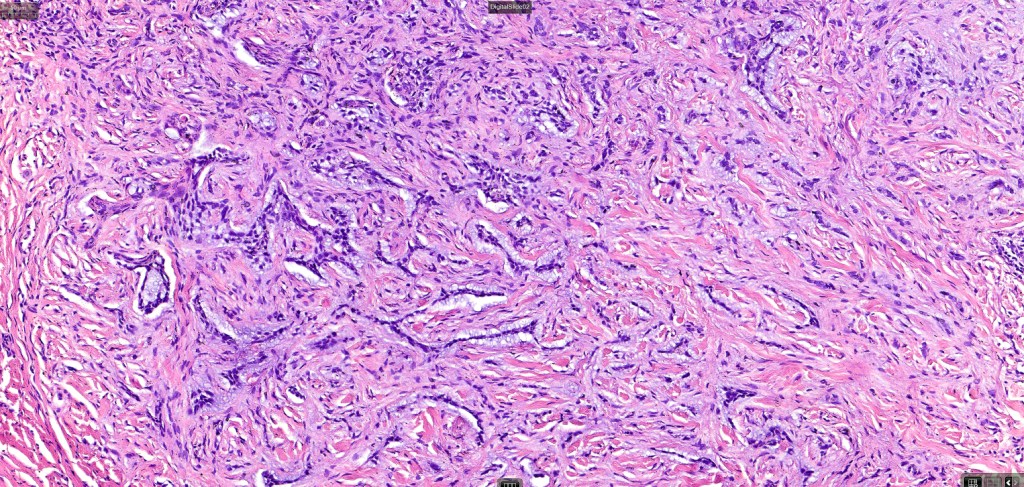

•Both epithelial & fibrous stromal components

•The epithelial component is composed of uniform small, basophilic devoid of desmosomes

•Retraction artifact with stromal mucin

•A wide variety of histological variants are possible including nodular, nodulocystic, ulcerative, superficial, micronodular, infiltrating/infiltrative, keratotic, basosquamous, pigmented, morpheaform, keloidal, clear-cell, signet-ring cell & granular cell variants, BCC with monster cells, BCC with metaplastic features, BCC with matricial differentiation, basomelanocytic tumor (see separate blog), BCC with thickened basement membrane, BCC with carcinoid-like nuclear palisading & these are illustrated below